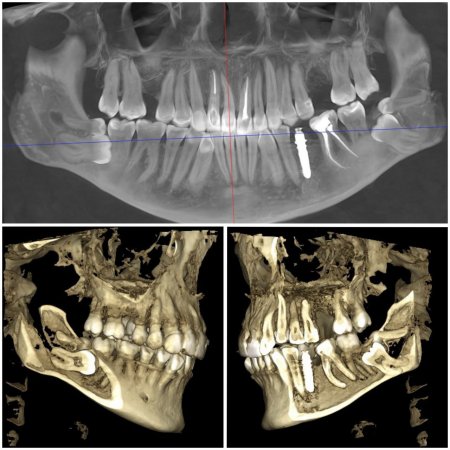

Ключ до успішної імплантації — точна діагностика. В арсеналі “ДентЛюкс” є один із найкращих КТ-апаратів в Україні— PLANMECA VISO G7.

Завдяки 3D-діагностиці імпланти встановлюються з ідеальною точністю. Результат — безпечно, комфортно та надовго.